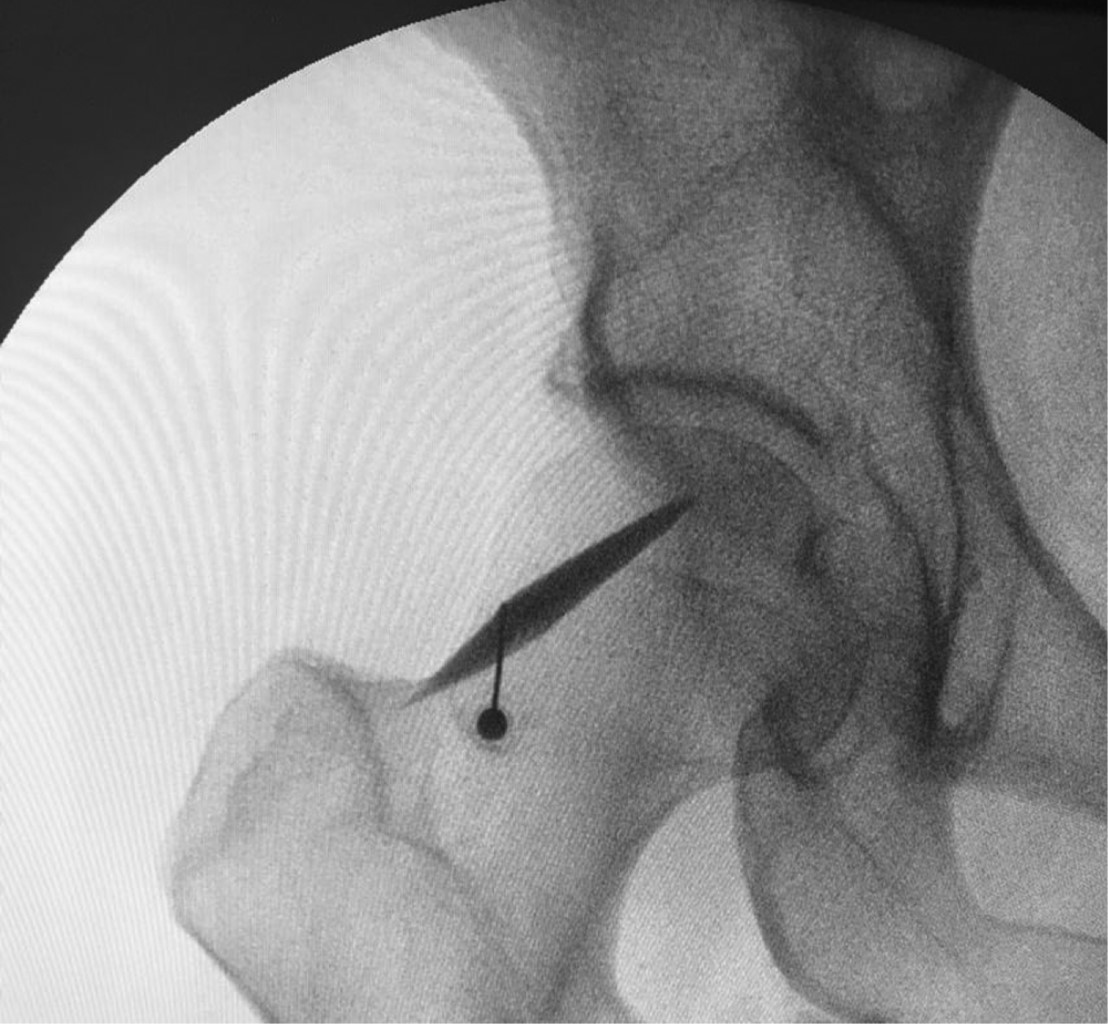

Mujer de 52 años de edad con dolor de glúteo derecho con irradiación a la rodilla y pie de tres meses de evolución, refiere que el dolor aumenta al estar sentada sin tolerar más de 20 minutos. El examen físico: EVA 7/10 y Oswestry 42, Lasegue negativo, FABER y FADIR positivos, reflejos normales, estudios de imagen (RMN) evidenciaron hernia lumbar L 5/S1 sin compresión radicular (Figura 1), además de estudios de electromiografía, interpretado por neurofisiólogo, quien reporta irritación radicular L 5/S1, debido a resultados se inicia tratamiento médico con pregabalina de 75 mg cada 12 horas, acetaminofén/tramadol cada 12 horas, y terapia física y rehabilitación, a pesar de tratamiento durante seis semanas persiste con sintomatología, sin mejoría clínica, porque se realiza infiltración foraminal de S1 guiada por fluroscopia, sin presentar mejoría. Se realiza nueva exploración clínica, y en esta oportunidad presenta prueba FADIR con dolor aumentado, y dolor a la palpación en región glútea, por lo que se realiza RMN de pelvis encontrando asimetría del músculo piramidal, con mayor tamaño de lado derecho (Figura 2), hallazgos que sugieren síndrome piramidal, por lo que se realizó infiltración diagnóstica, la cual fue positiva con alivio del dolor por tres meses (Figura 3). Después inicia otra vez con dolor, nuevamente con prueba FADIR positiva y un EVA de 6/10, se ofrece tratamiento quirúrgico a paciente el cual acepta.

Figura 1

Figura 2

Figura 3

Figura 4